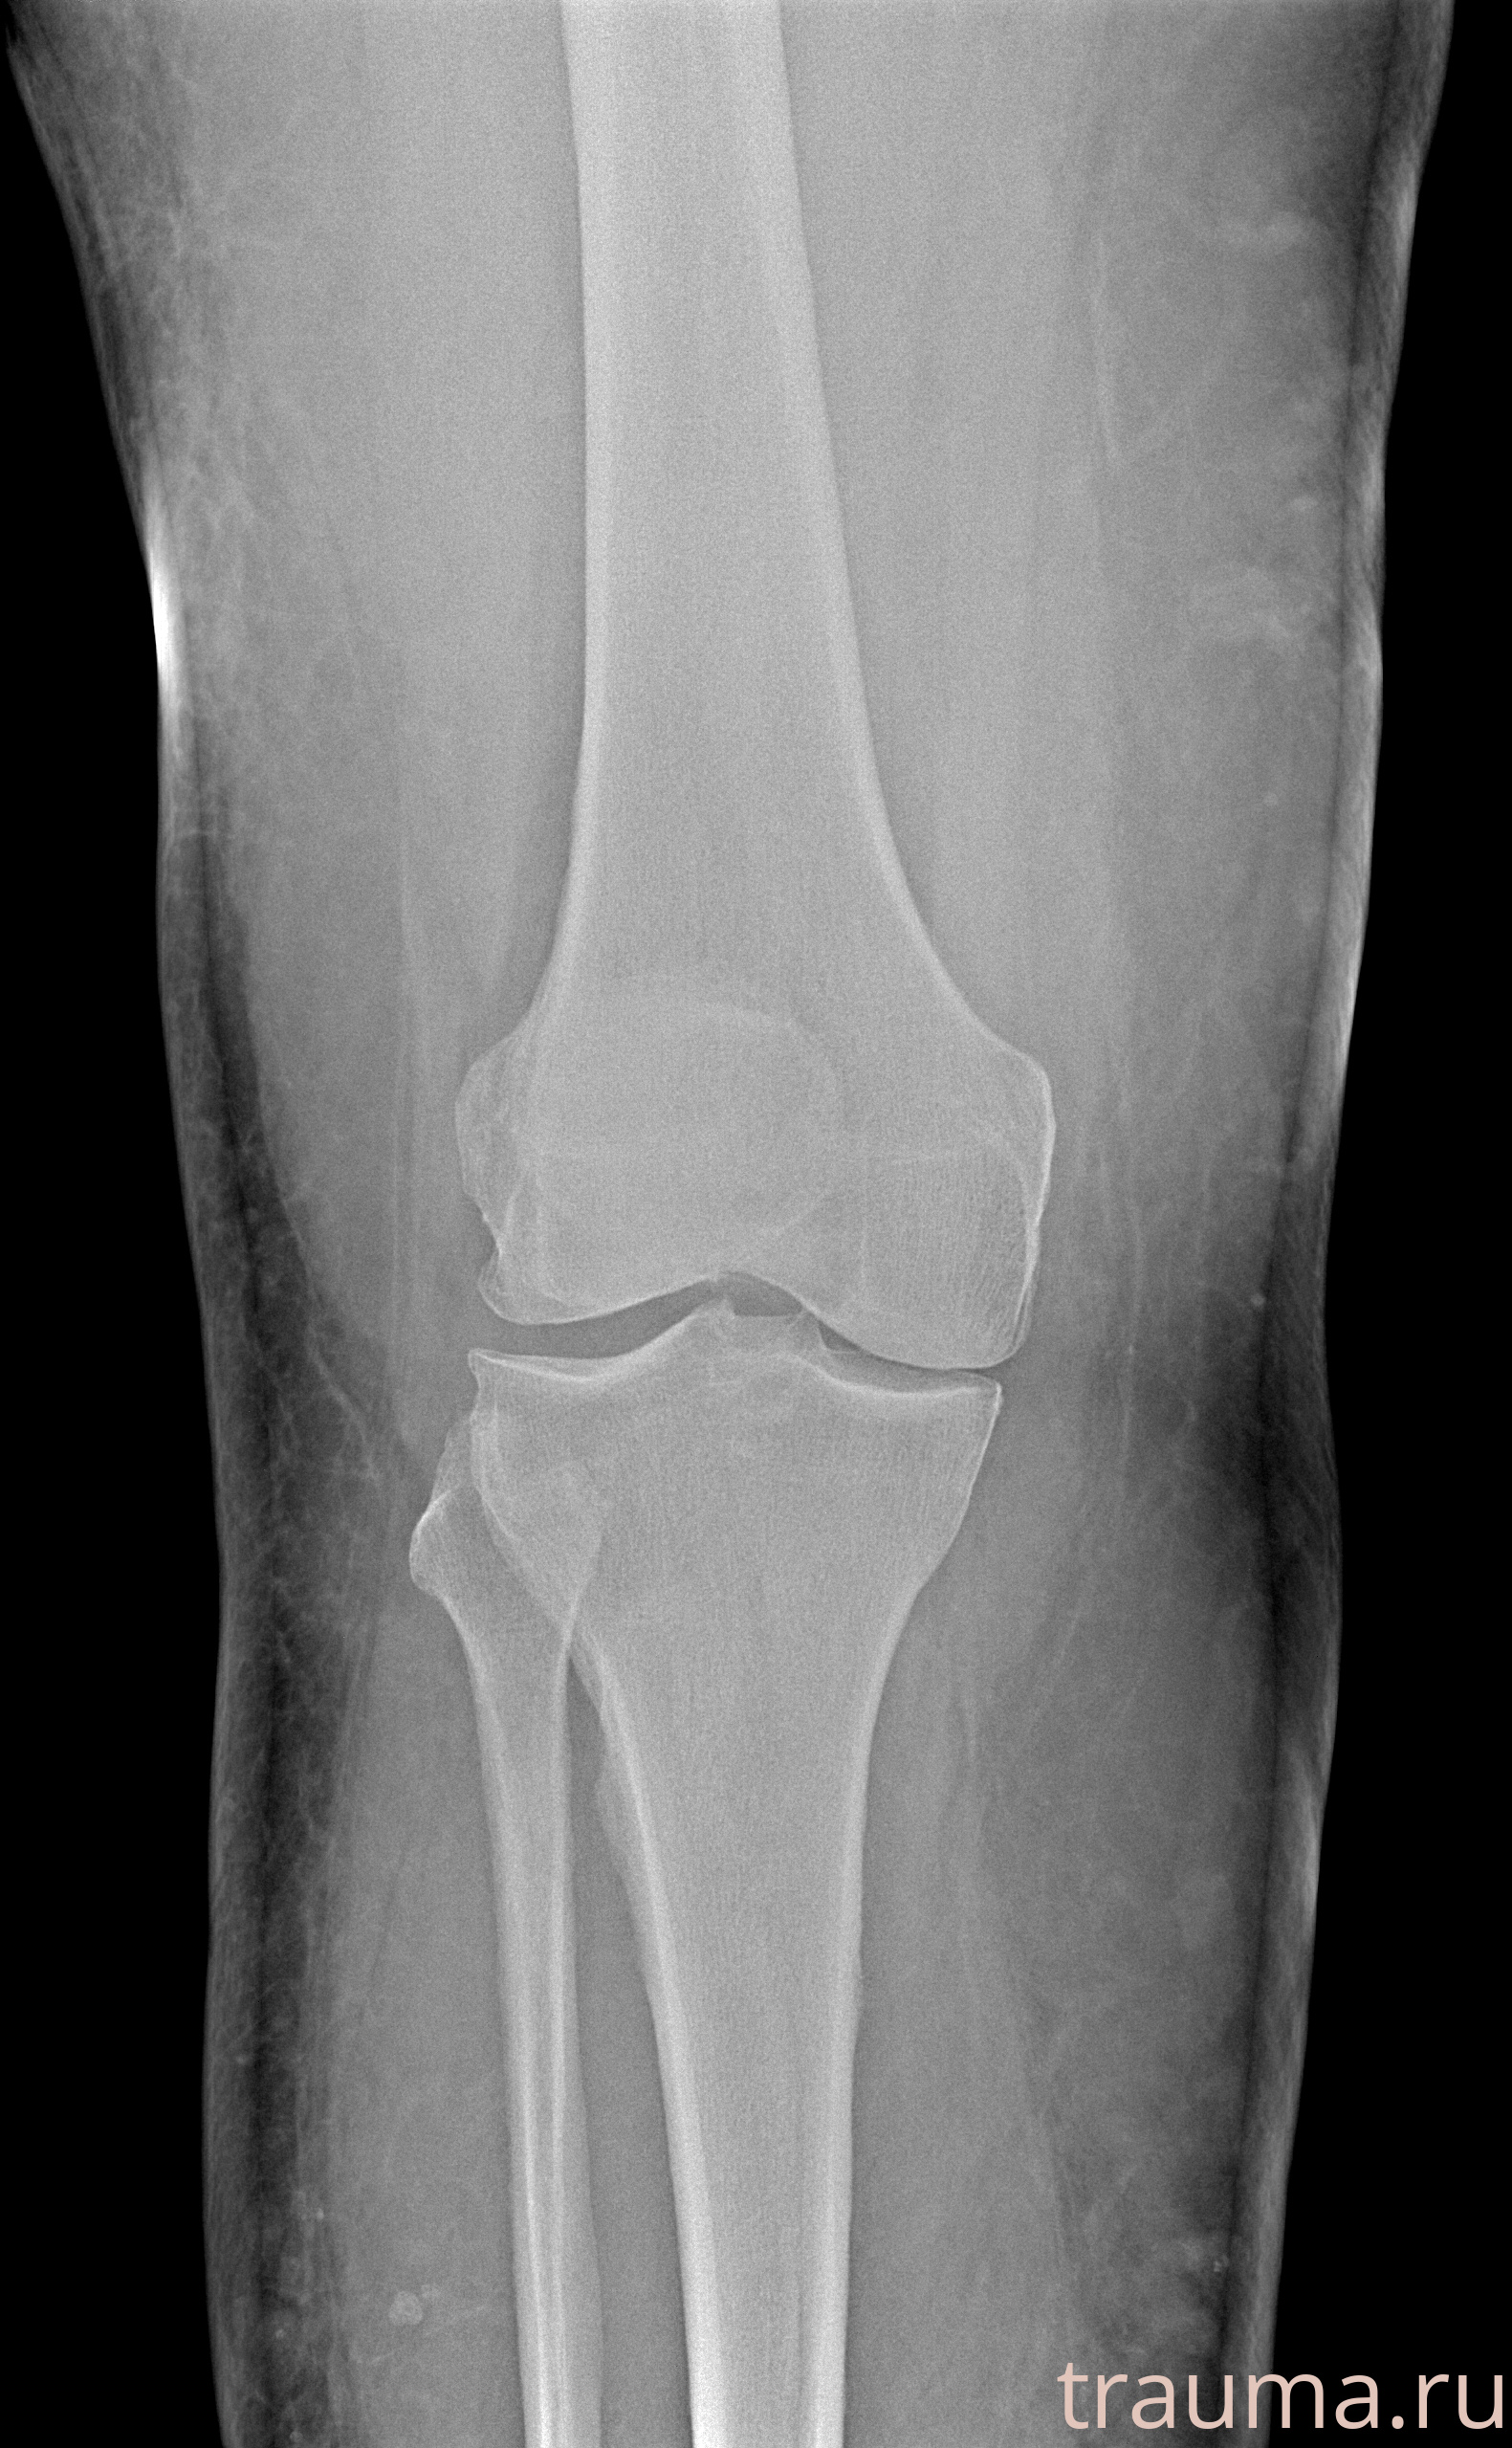

Рентгенограммы

Рентген на дому: по вашему адресу приезжает врач-рентгенолог, травматолог-ортопед с мобильным рентгеновским аппаратом, проводит диагностику травмы или заболевания, делает необходимые рентгенограммы, дает рекомендации по дальнейшему лечению. Получить качественные снимки в домашних условиях возможно благодаря уникальной методике, разработанной МосРентген Центром для института  Склифосовского